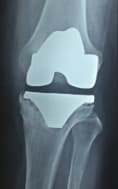

Үе дайрсан ясны анхдагч хавдар, ясны дутмагшлын үед хийгдэх мэс засалimage8Үе дайрсан ясны анхдагч хавдар, ясны дутмагшлын үед хийгдэх мэс засалimage9

Зураг 1. Гадна харагдах байдал: Зүүн дунд чөмөгний өвдөгний үе орчмын ясны хавдар, хавдар задар үхэжсэн байна.

Үе дайрсан ясны анхдагч хавдар, ясны дутмагшлын үед хийгдэх мэс засалimage10

А. Мэс засал хийсэн өвдөгний үе

Үе дайрсан ясны анхдагч хавдар, ясны дутмагшлын үед хийгдэх мэс засалimage11

Б. Бүтэн биеийн рентген зураг

Зураг 2. Мэс заслын дараах рентген зураг

Хавдрын улмаасмэс хийлгэсэнөвчтөнгүүд мэс заслын дараа 2-3 хоногийн дотор шууд гишгэж явж, мөчдийн үйл ажиллагаа хурдан сэргэж эхний 1 сард үений хөдөлгөөний далайц хэвийн болсон .